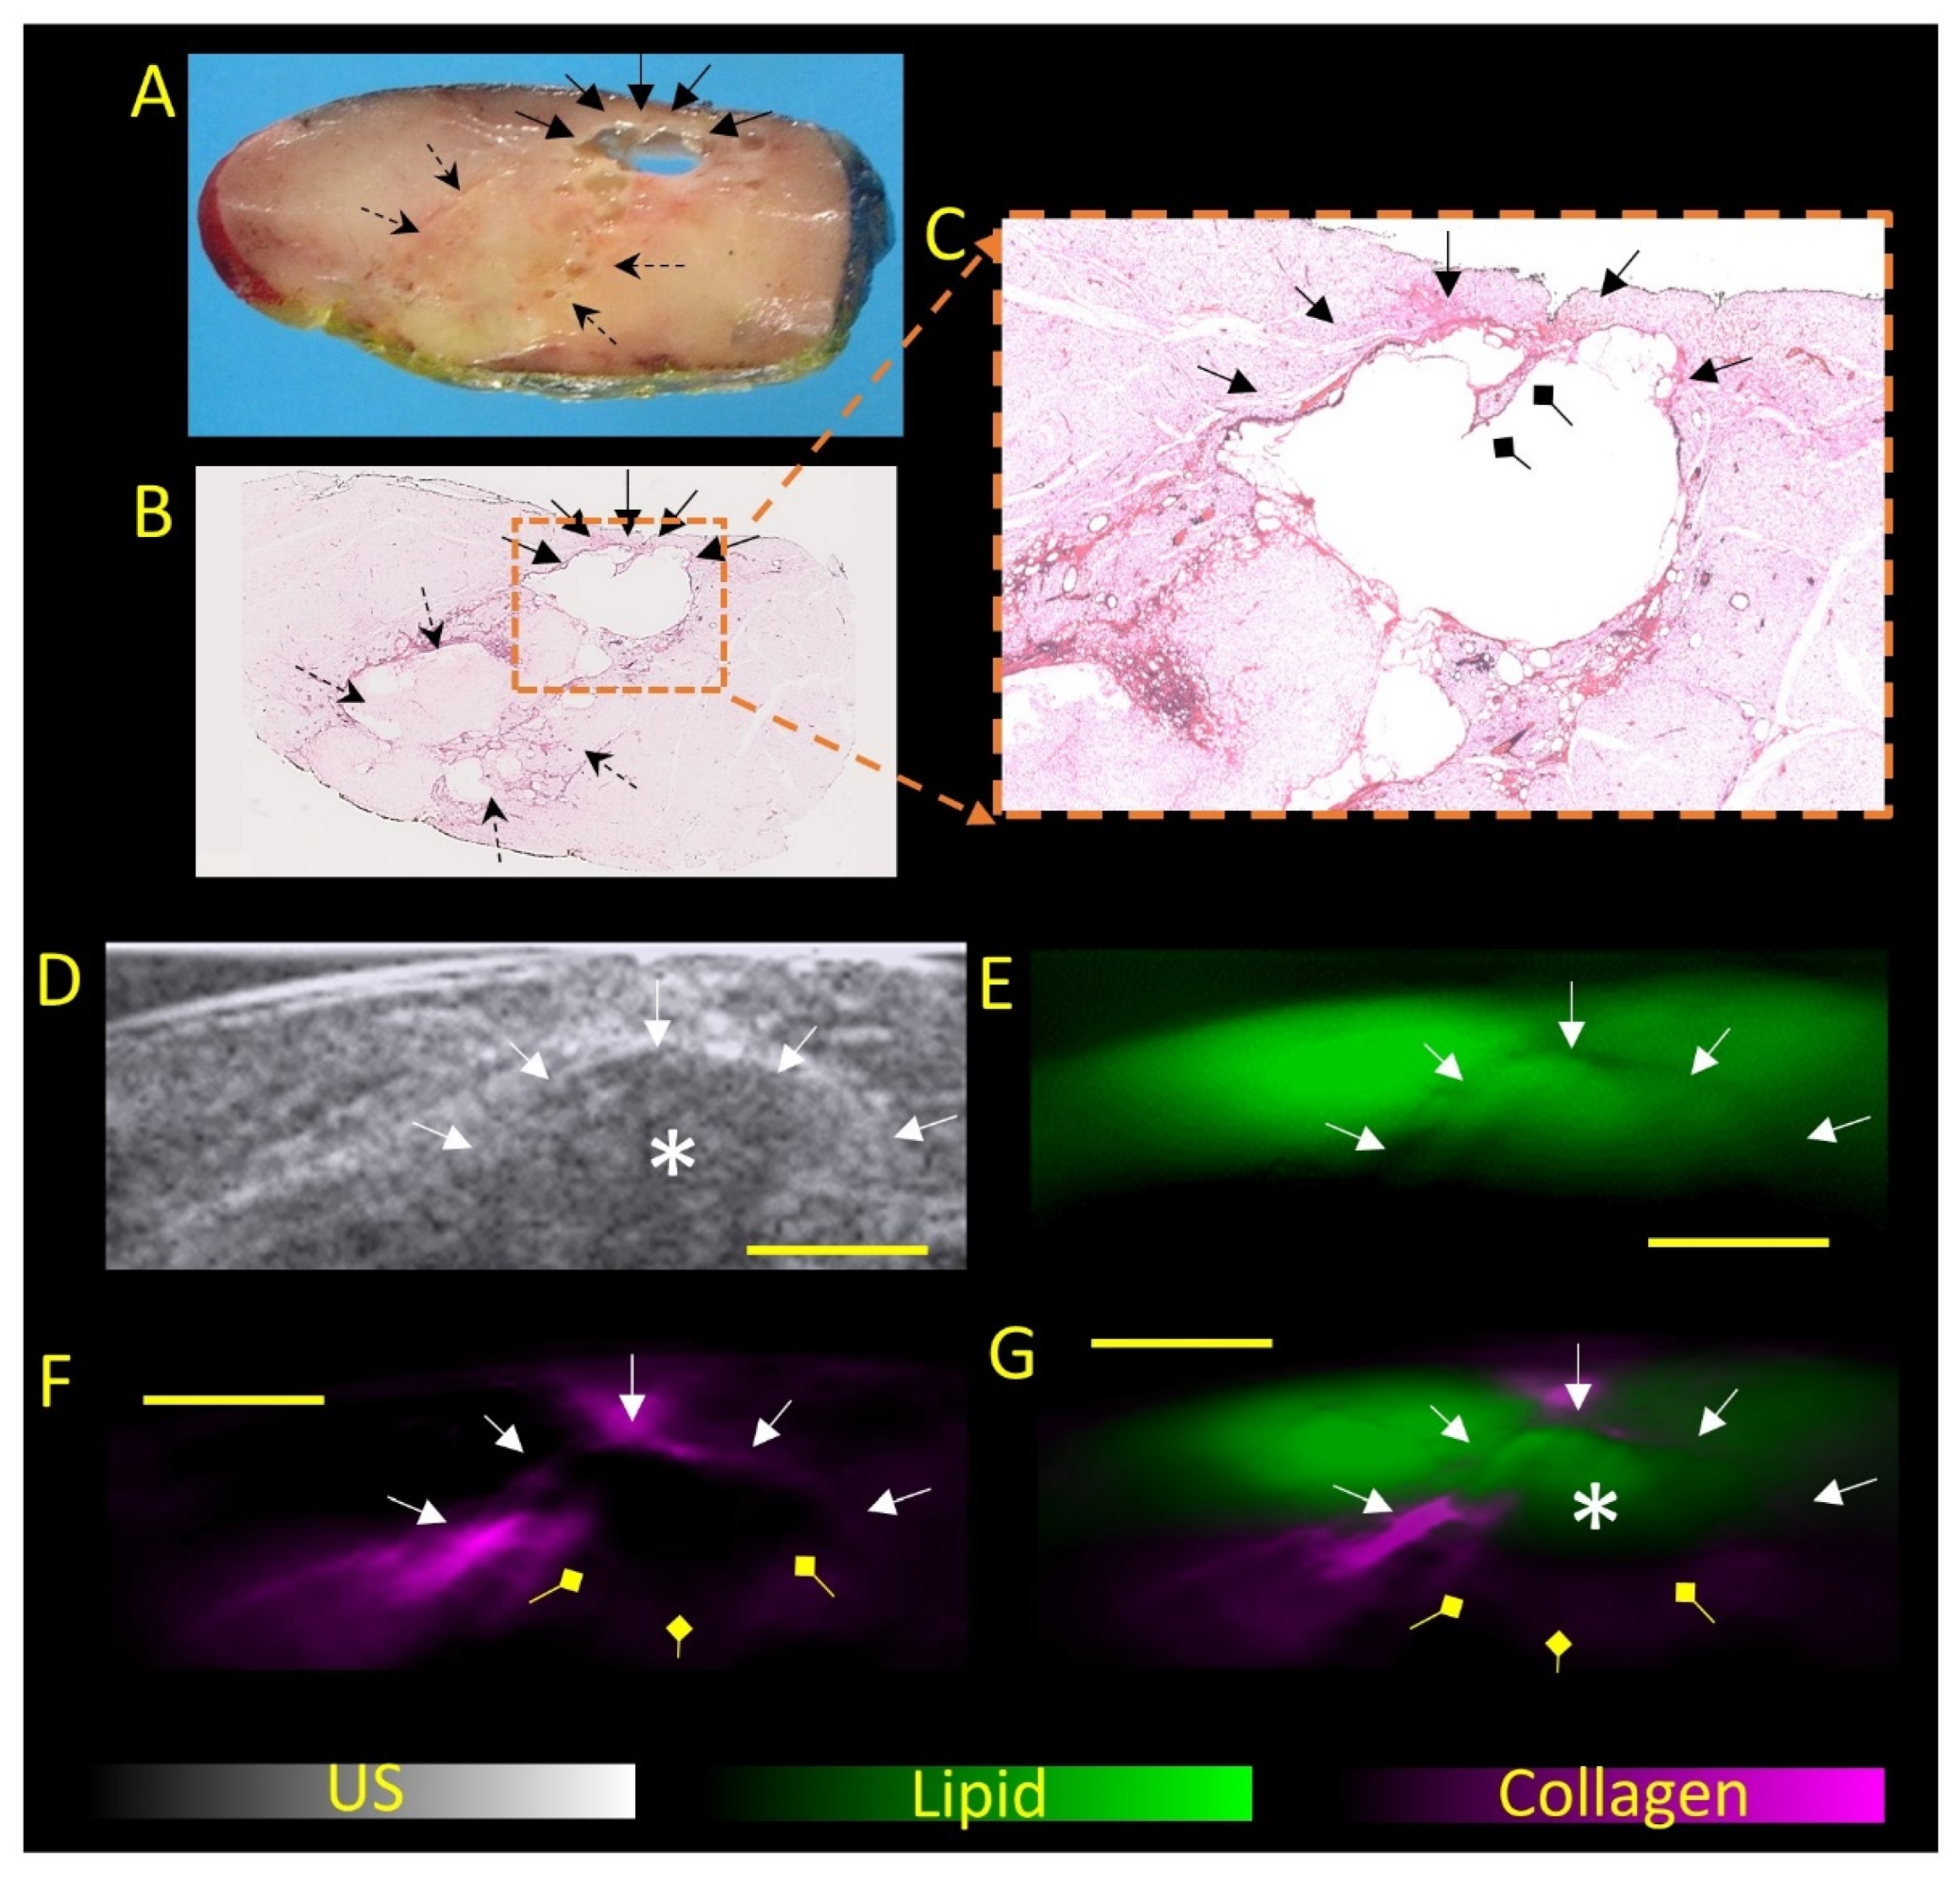

- Balasundaram, G.; Goh, Y.; Moothanchery, M.; Attia, A.; Lim, H.Q.; Burton, N.C.; Qiu, Y.; Putti, T.C.; Chan, C.W.; Hartmann, M.; et al. Optoacoustic characterization of breast conserving surgery specimens—A pilot study. Photoacoustics 2020, 19, 100164. [Google Scholar] [CrossRef]

- Goh, Y.; Balasundaram, G.; Tan, H.M.; Putti, T.C.; Tang, S.W.; Ng, C.W.Q.; Buhari, S.A.; Fang, E.; Moothanchery, M.; Bi, R.; et al. Biochemical “decoding” of breast ultrasound images with optoacoustic tomography fusion: First-in-human display of lipid and collagen signals on breast ultrasound. Photoacoustics 2022, 27, 100377. [Google Scholar] [CrossRef]